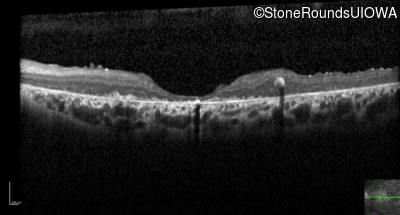

Optical Coherence Tomography - Left - 20/400 sc

Exemplar / OCT Stack